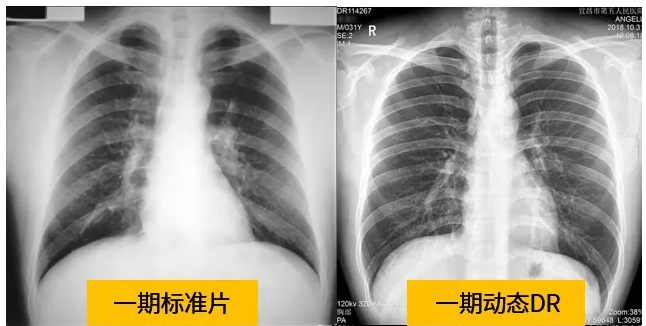

动态dr的拍摄效果图

动态DR技术与普通DR单截面诊断的不同就是在操作过程中,可以随时切换成透视模式,透视/摄片模式实时切换,对阴影进行多角度动态的鉴别。实时点片、实时回放、连续点片等多功能大大的增加了初诊的准确率。在小阴影的形态和性质,特别是不规则小阴影的判断方面提升,从而达到提高胸片整体判断准确性。

根据数据统计表现,利用动态dr进行检查的话,图像的质量和辐射剂量相对较少。并且动态DR在图像清晰度和射线穿透力方面完全能达到尘肺诊断的要求。这种检查效果的精准和便捷性是和普通设备不一样的,动态DR尘肺摄影应用于尘肺疾病诊断中,可以提高检出率及优片率。